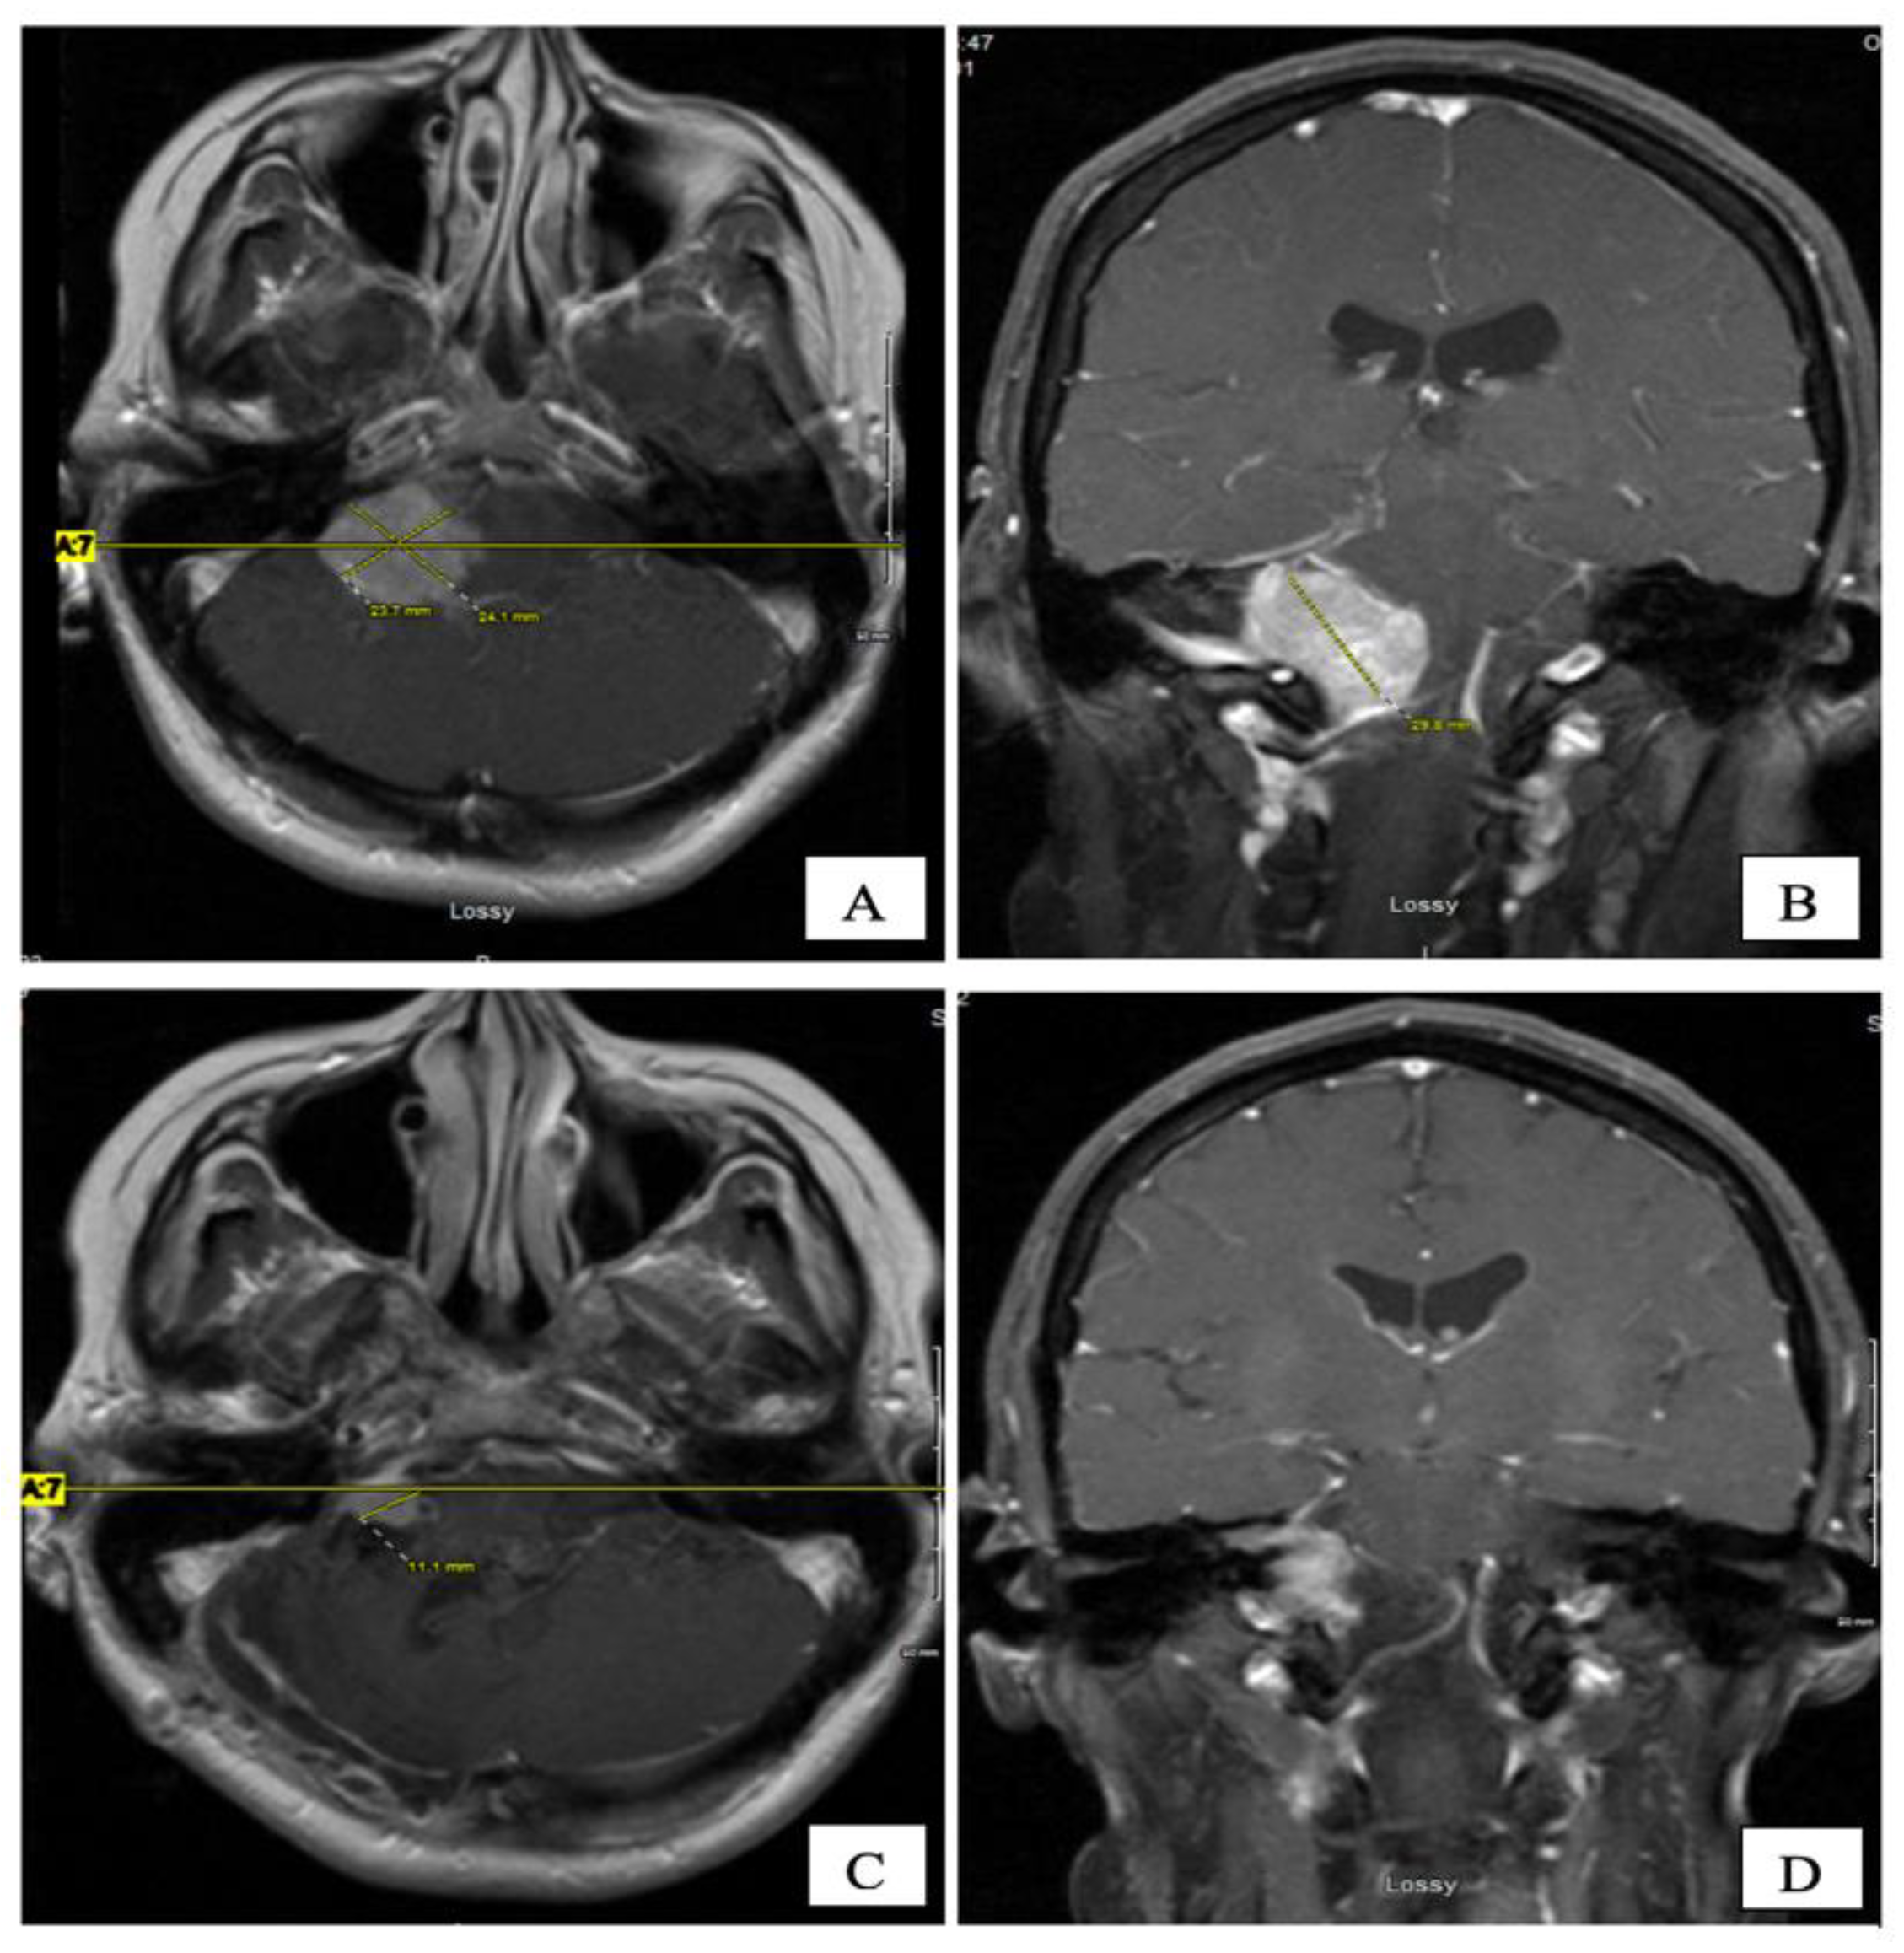

The patient tolerated SRS well, with no acute or late toxicity. Over the next five years, she had gradual clinical improvement in her gait, swallowing and facial palsy. Additionally, she had complete resolution of her headaches and improvement in her voice function. Serial MRIs revealed her tumour regression with the relief of mass effect on the brainstem (Figure 5). There were no T2/Flair changes (acute or late edema) in the brainstem post-treatment.

Figure 5. Post-gadolinium T1-W MRI at four years post CK, on axial (A) and coronal (B) planes. The CPA tumour shrank to 12 × 12 mm.